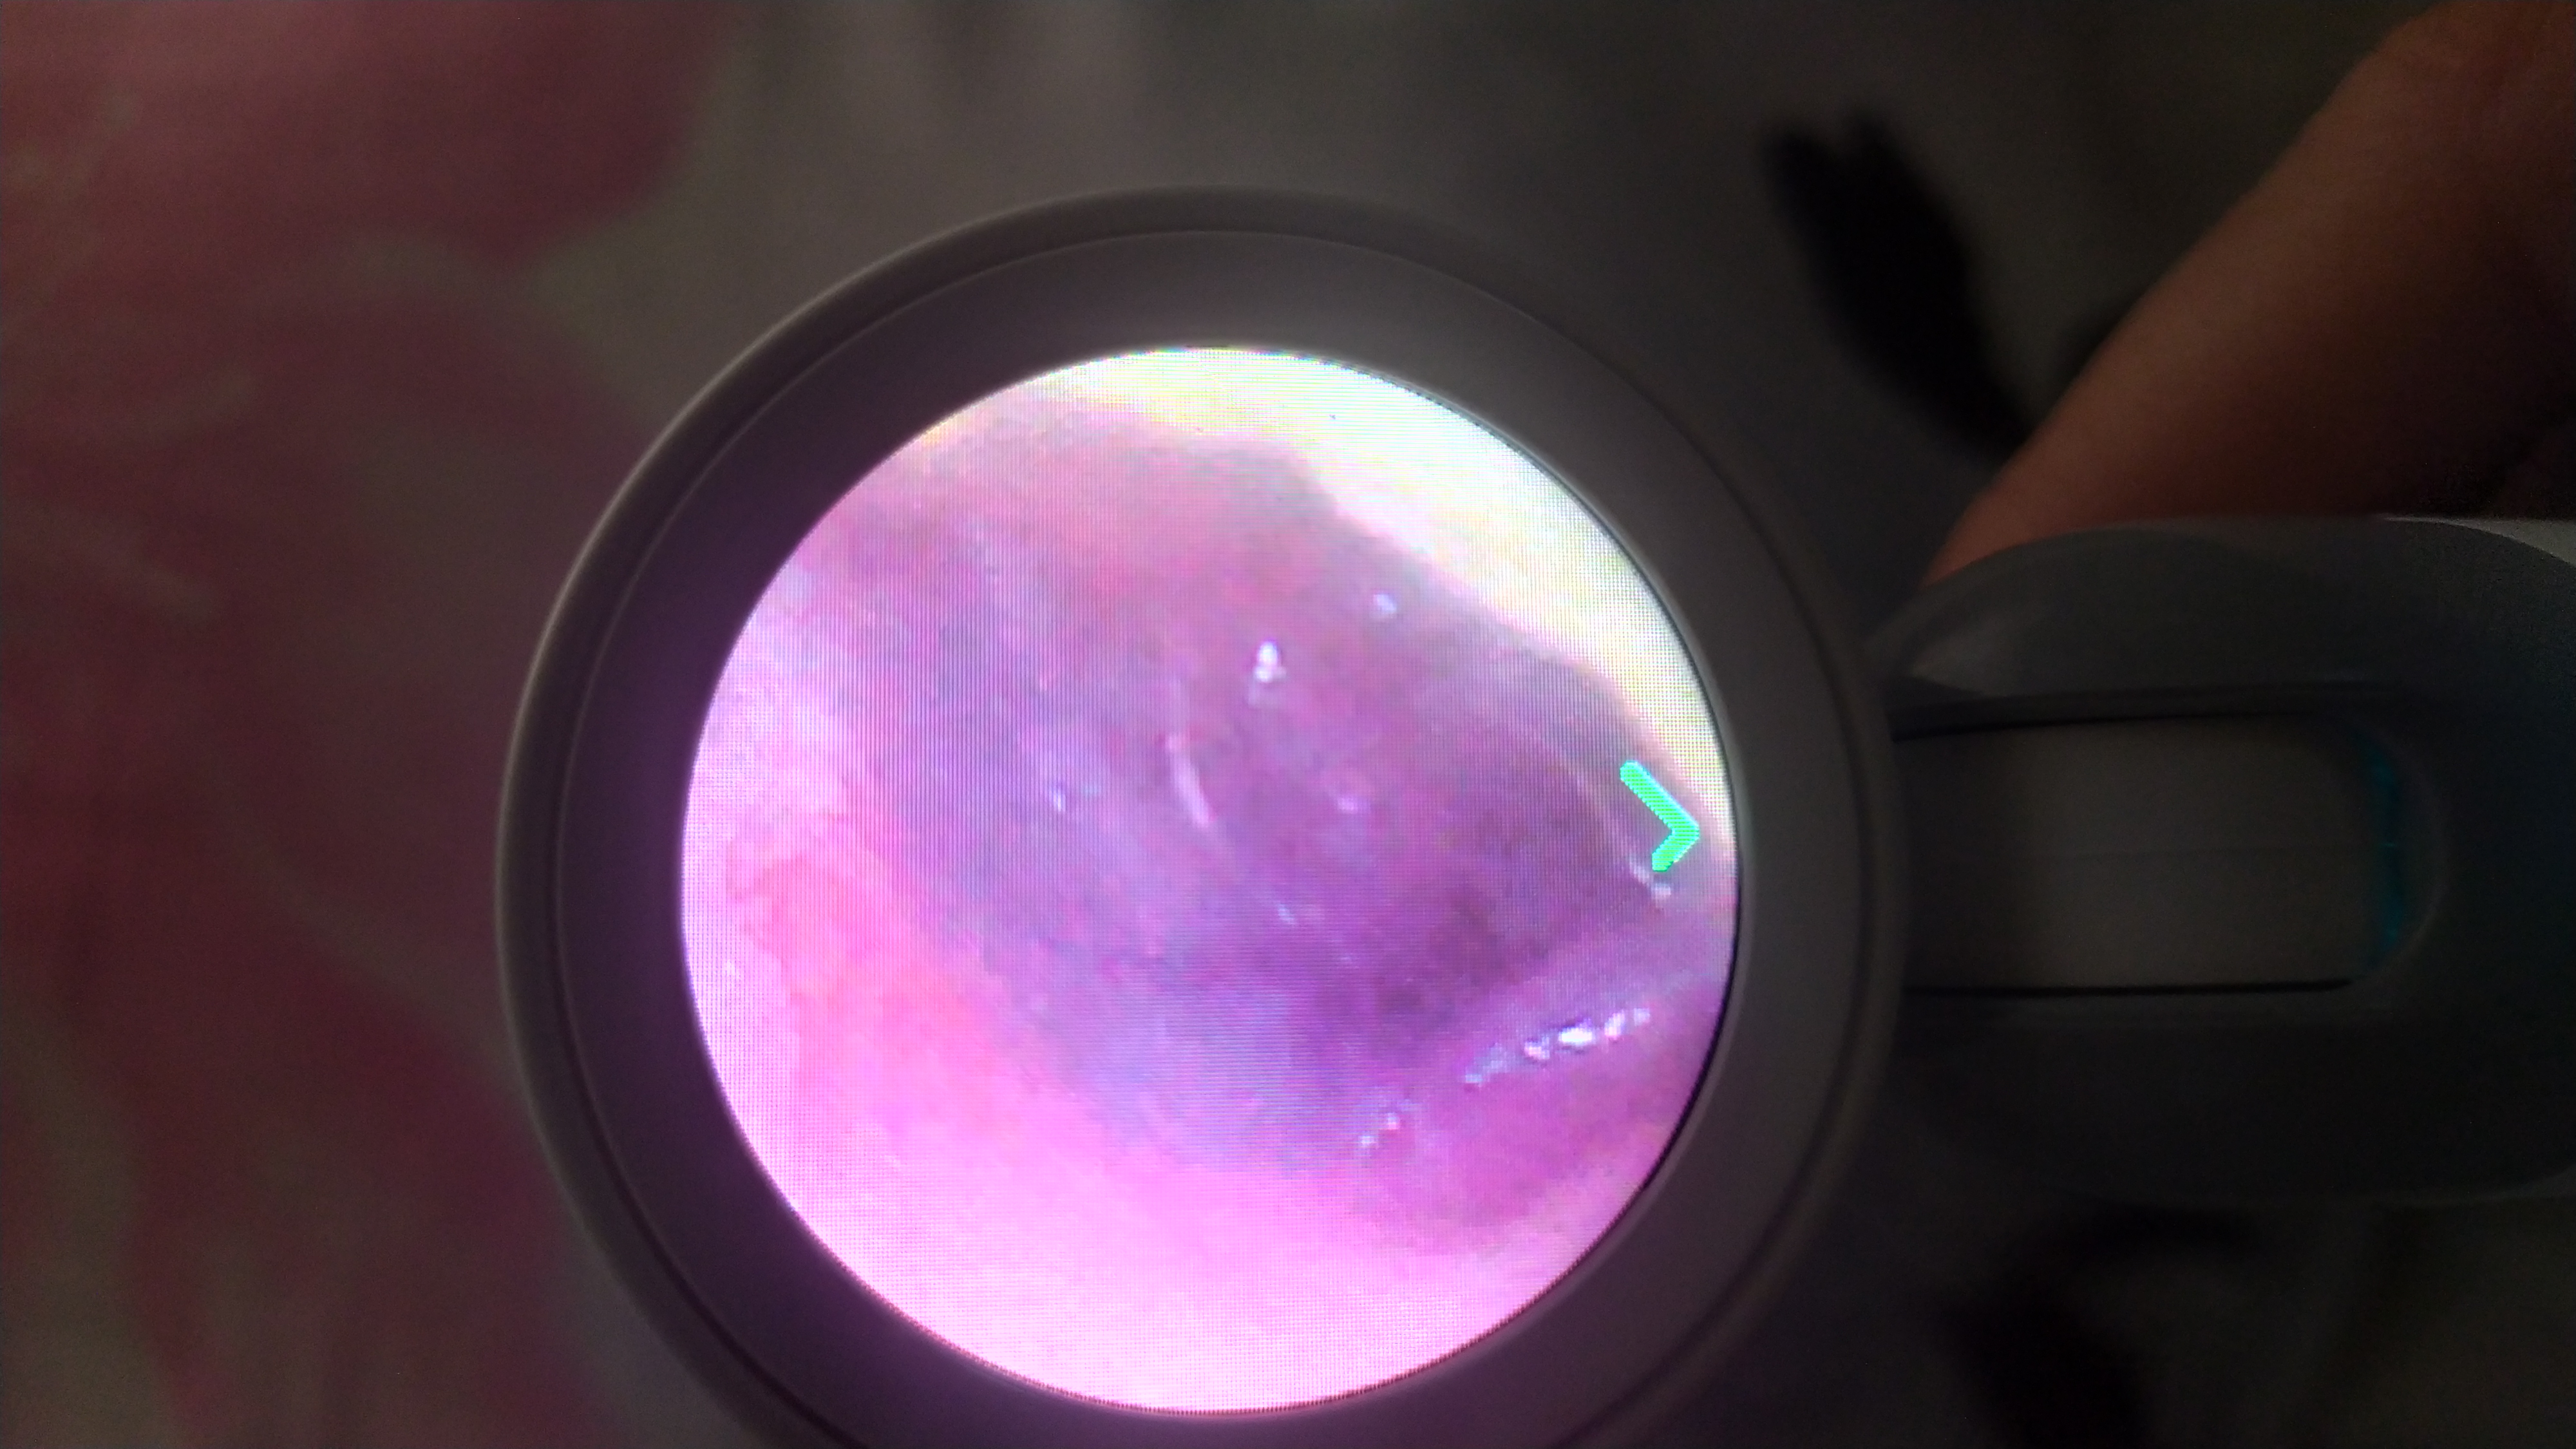

Сделала сегодня фото ушей ребенка сама цифровым отоскопом. Подскажите пожалуйста есть ли отит и есть ли перфорация барабанной перепонки? Чем лечить уши ребенку двух лет в случае перфорации барабанной перепонки?